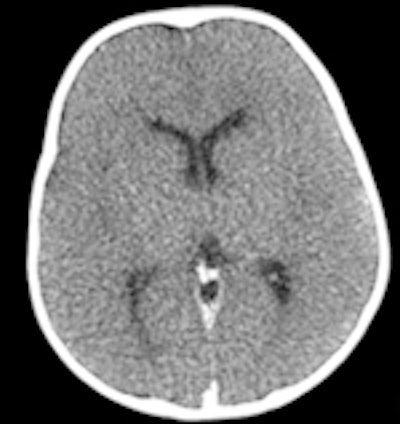

CT and MRI exams were performed during evening and night shifts at times when scanners were not in use for the hospitals' patients. The bodies, contained in sealed body bags, were imaged in the supine position. Two radiologists first independently interpreted the exams, preparing individual reports. They subsequently prepared a consensus report. Additionally, brain scans were reported by a specialist neuroradiologist, and a specialist cardiac radiologist also interpreted findings and prepared a report. All radiologists limited their reports to noting only findings that could pertain to cause of death.

Based on their findings, the radiologists determined that an autopsy could have been avoided for 34% of the cases based on CT exam reports, 42% based on MRI reports, and 48% based on consensus reports. In many cases, imaging proved to be better than autopsy in detecting pneumothorax, intracranial pathologies, and some fractures, the authors wrote.